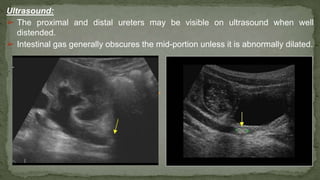

Ultrasound:

➢ The proximal and distal ureters may be visible on ultrasound when well

distended.

➢ Intestinal gas generally obscures the mid-portion unless it is abnormally dilated.